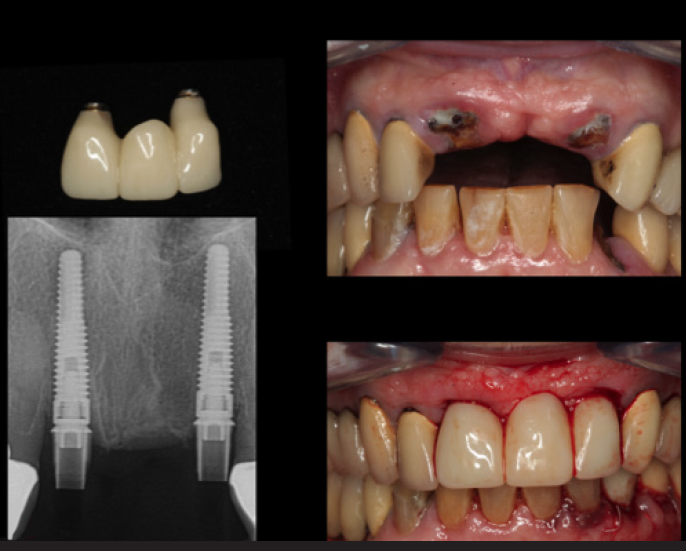

Some situations within dentistry require creativity and use of technologic innovations to deliver esthetic and functional solutions for patients who may not want to spend much time in the dental office or may have difficulties with transportation to the dental facility. There are means of expediting treatment, particularly for the aging population. Figure 5 depicts a 94-year-old patient who had class 3 fractures with caries of dentin and cementum (non-restorable). With the aid of CBCT, photography, and intraoral scanning of a virtual model, a clinician can implement a fully guided surgical guide, abutments, and long-term polymethyl methacrylate (PMMA) provisional to be fabricated in a laboratory and delivered within 7 days. For this patient, extractions were completed atraumatically, implants seated with a fully guided surgical guide, ti-base abutments seated and verified with a periapical radiograph, and PMMA provisional placed on the same day and secured with screw retention (Figure 6).

Fig 5. Class 3 fractures with caries of dentin and cementum (nonrestorable)

(left) and guided smile synchronized to extract, place, and

restore 3.5 x 16 mm implants.

Figure 5

Fig 6. Ti-base abutments were seated

and verified with a periapical radiograph, and a PMMA provisional

placed on the same day and secured by screw retention.

Figure 6